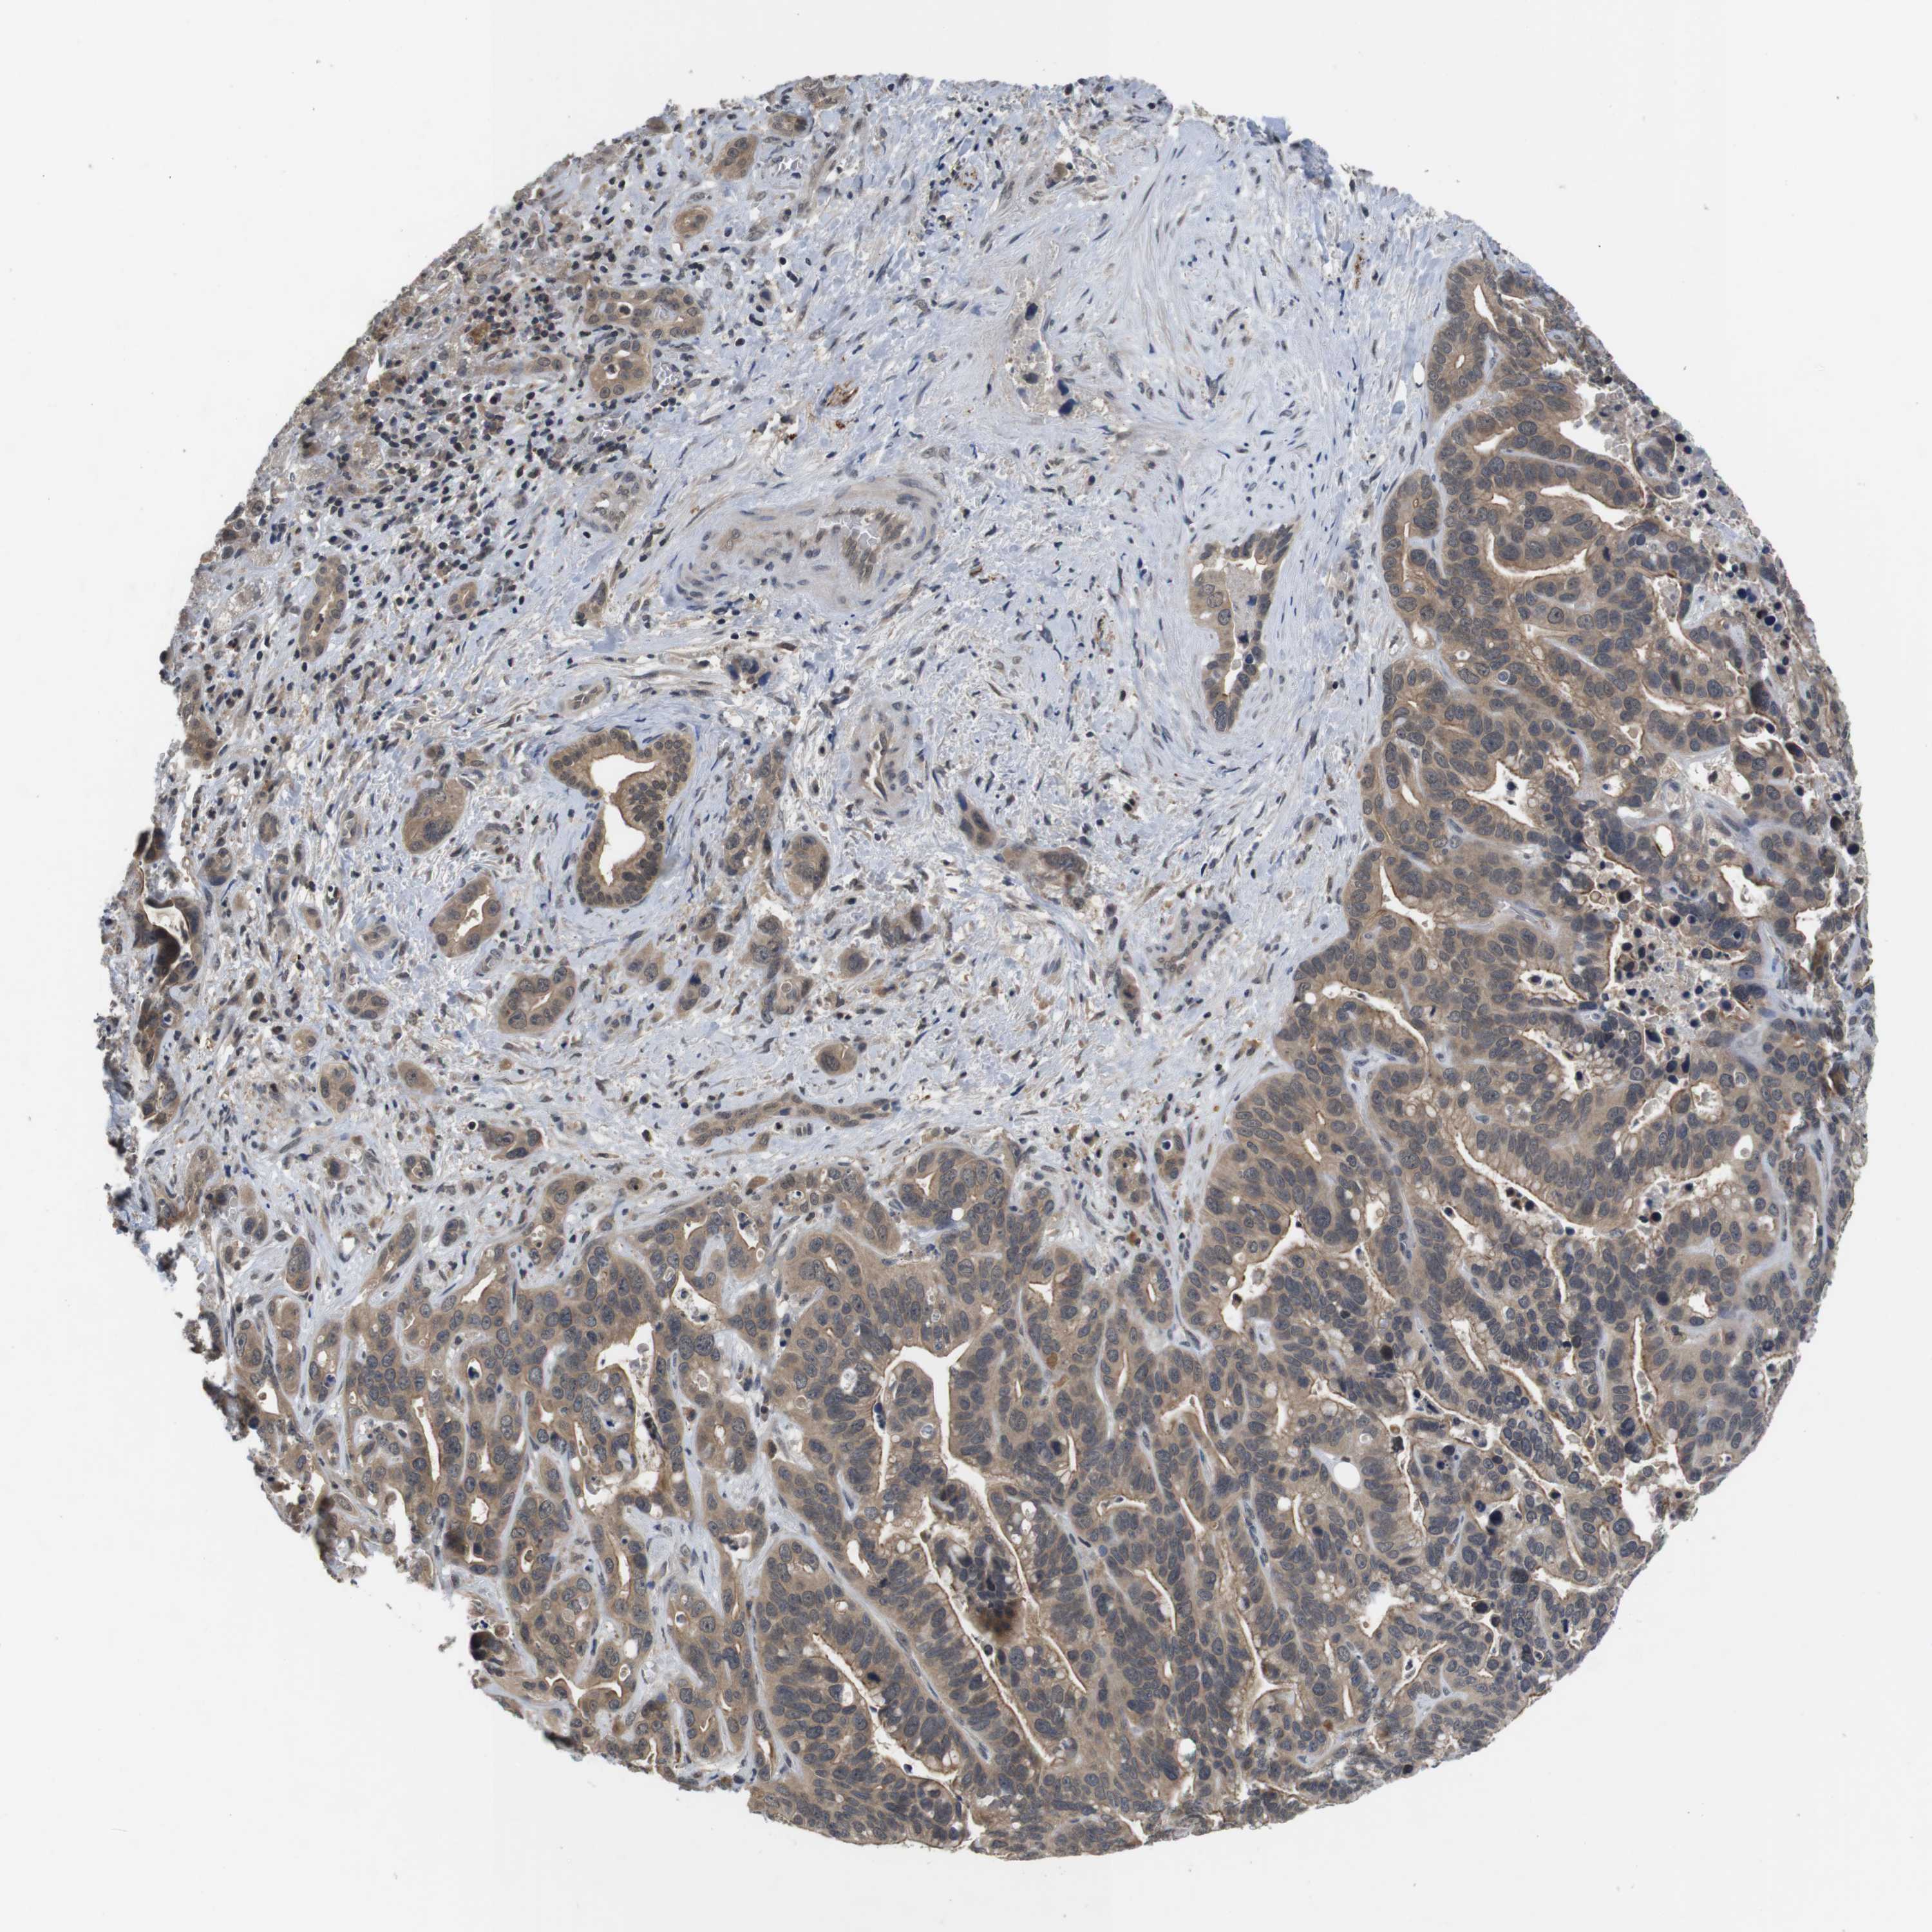

LIVER CANCER - Protein expressioni

A mouse-over function shows sample information and annotation data. Click on an image to view it in a full screen mode. Samples can be filtered based on level of antibody staining by selecting one or several of the following categories: high, medium, low and not detected. The assay and annotation is described here.

Antibody stainingi

Antibody staining in the annotated cell types in the current human tissue is reported as not detected, low, medium, or high, based on conventional immunohistochemistry profiling in selected tissues. This score is based on the combination of the staining intensity and fraction of stained cells.

Each image is clickable and will lead to virtual microscopy that enables deeper exploration of all samples and also displays staining intensity scores, fraction scores and subcellular localization as well as patient and tissue information for each sample.

Antibody HPA001464

Antibody CAB010209

Staining

High

Medium

Low

Not detected

Intensity

Strong

Moderate

Weak

Negative

Quantity

>75%

75%-25%

<25%

None

Location

Nuclear

Cytoplasmic/membranous

Cytoplasmic/membranous,nuclear

Cholangiocarcinoma

Carcinoma, Hepatocellular, NOS